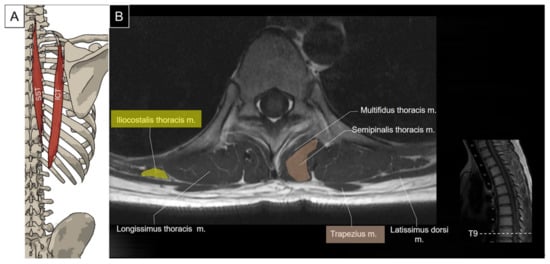

5.1. Iliocostalis Thoracis, Longissimus Thoracis, Semispinalis Thoracis, and Thoracic Multifidus

5.1.1. Anatomy